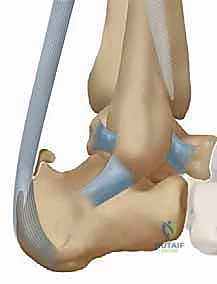

لفهم طبيعة التهاب وتر أخيل التكلسي وكيفية علاجه جراحياً بنجاح، من الضروري جداً أن نلقي نظرة عميقة ومفصلة على التشريح المعني في هذه المنطقة الحساسة من الجسم. وتر أخيل، المعروف أيضاً بالوتر العقبي (Calcaneal Tendon)، هو الحبل الليفي السميك والقوي الذي يربط عضلات الساق الخلفية (عضلة الساق التوأمية Gastrocnemius والعضلة النعلية Soleus) بعظم الكعب (العقب Calcaneus). هذا الوتر حيوي لعملية الثني الأخمصي (Plantar flexion)، وهي الحركة التي تسمح لنا بالوقوف على أطراف أصابعنا ودفع أنفسنا إلى الأمام أثناء المشي أو الجري.

يدخل وتر أخيل ويثبت نفسه في النصف السفلي من الحدبة الخلفية لعظم الكعب. هذه المنطقة ليست ناعمة، بل تتميز بسطح خشن متعرج، مما يشير إلى وجود شبكة واسعة وكثيفة من ألياف شاربي (Sharpey's fibers). هذه الألياف هي عبارة عن حزم قوية من الكولاجين التي تخترق نسيج العظم لتثبت الوتر بإحكام شديد. هذه الألياف هي مفتاح الثبات والمتانة، وهي المنطقة التي تتعرض لأكبر قدر من الشد الميكانيكي، مما يجعلها الموقع الأول لحدوث التمزقات الدقيقة (Micro-tears) وبدء عملية التكلس.

الجراب خلف العقب (Retrocalcaneal Bursa) وعلاقته بالالتهاب

فوق نقطة اتصال الوتر مباشرة، يوجد النصف العلوي من الحدبة الخلفية لعظم الكعب، والذي يتميز بسطح أملس ومائل. يشكل هذا السطح الأملس الحدود الأمامية لتركيب تشريحي هام يُعرف بـ الجراب خلف العقب (Retrocalcaneal Bursa). هذا الجراب هو عبارة عن كيس زلالي صغير مملوء بسائل لزج، يعمل كوسادة تشحيم بين وتر أخيل وعظم الكعب، وظيفته الأساسية هي تقليل الاحتكاك أثناء انقباض وانبساط الوتر.

في حالات التهاب الوتر التكلسي، وبسبب الاحتكاك المستمر بالنتوءات العظمية المتكونة (مثل تشوه هاغلوند Haglund's Deformity)، غالباً ما يصاحب ذلك التهاب حاد ومزمن في هذا الجراب (Bursitis)، مما يؤدي إلى تضخمه وامتلائه بالسوائل الالتهابية، وهو ما يفسر التورم الواضح والألم النابض الذي يشعر به المريض في مؤخرة الكعب.